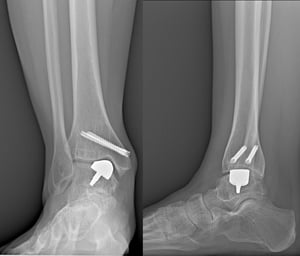

Sono, poi, fondamentali le indagini di imaging ed in particolare le radiografie dei piedi e delle caviglie in carico bilaterale (eseguite stando in piedi).

La radiografia in carico è imprescindibile per il corretto studio della deformità.

È molto utile avere a disposizione l’immagine anche del lato controlaterale, per poter studiare l’anatomia originaria del paziente, da sano.

Infine, la TAC è l’esame che permette di studiare la qualità dell’osso e di verificare la reale affidabilità dell’intervento, in quanto una protesi, per avere successo, deve appoggiare su osso di qualità sufficiente a garantire la stabilità dell’impianto stesso.